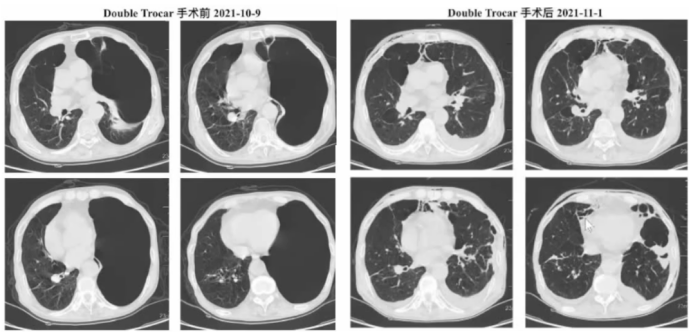

2所示为2021年笔者团队开展的第3例内科胸腔镜下肺大疱减容术患者的影像学,术前患者左肺巨大肺大疱;术后1个月复查可见左肺肺大疱完全消失,被压缩的肺明显膨胀,肺大疱减容后边缘有瘢痕形成。因为没有切除肺大疱,所以影像学中“不张”处是塌陷肺大疱的表现(方法即为戳卡手术模式)

图片

2  “Double-Trocar”手术前后患者影像学变化